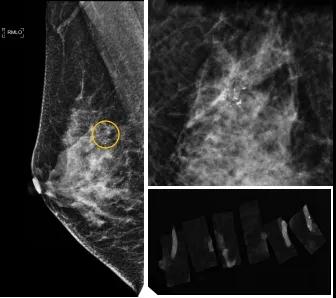

小到1—2mm的鈣化也能活檢!西安國(guó)際醫(yī)學(xué)中心醫(yī)院采用精準(zhǔn)技術(shù)讓乳腺早癌無(wú)處可逃

46歲的某女士在西安國(guó)際醫(yī)學(xué)中心醫(yī)院體檢時(shí),行乳腺X線攝影(俗稱鉬靶)發(fā)現(xiàn)右乳可疑簇狀鈣化,分布范圍不到1厘米,臨床觸不到,超聲很難發(fā)現(xiàn),但是這種鈣化風(fēng)險(xiǎn)比較高,依據(jù)國(guó)際BI-RADS指南需要明確病理!

西安國(guó)際醫(yī)學(xué)中心醫(yī)院影像診療中心陳寶瑩副主任帶領(lǐng)的團(tuán)隊(duì),采用全數(shù)字化乳腺X線三維立體定位系統(tǒng)可實(shí)施。這個(gè)團(tuán)隊(duì)的成員大部分來(lái)自知名三甲醫(yī)院,有著十余年影像引導(dǎo)下乳腺介入診療的經(jīng)驗(yàn),X線引導(dǎo)穿刺定位和活檢例數(shù)居西北前列。為減少患者創(chuàng)傷,在詳細(xì)判讀了患者資料,并與患者及甲乳外科劉曉敏主任充分溝通的基礎(chǔ)上,團(tuán)隊(duì)確定采用全數(shù)字化乳腺X線三維立體定位系統(tǒng)下實(shí)施粗針活檢。

當(dāng)天,乳腺X線三維立體定位系統(tǒng)清晰顯示出了所有鈣化。為了獲取充足的組織量,保證病理診斷的準(zhǔn)確性,團(tuán)隊(duì)選用14G穿刺針并多點(diǎn)、多角度取材,組織取出后,又立即在高清標(biāo)本攝影系統(tǒng)中進(jìn)行投照,從而確定了取出組織中具有足夠的可疑鈣化。整個(gè)過(guò)程患者無(wú)任何不適,活檢結(jié)束后即回家觀察。